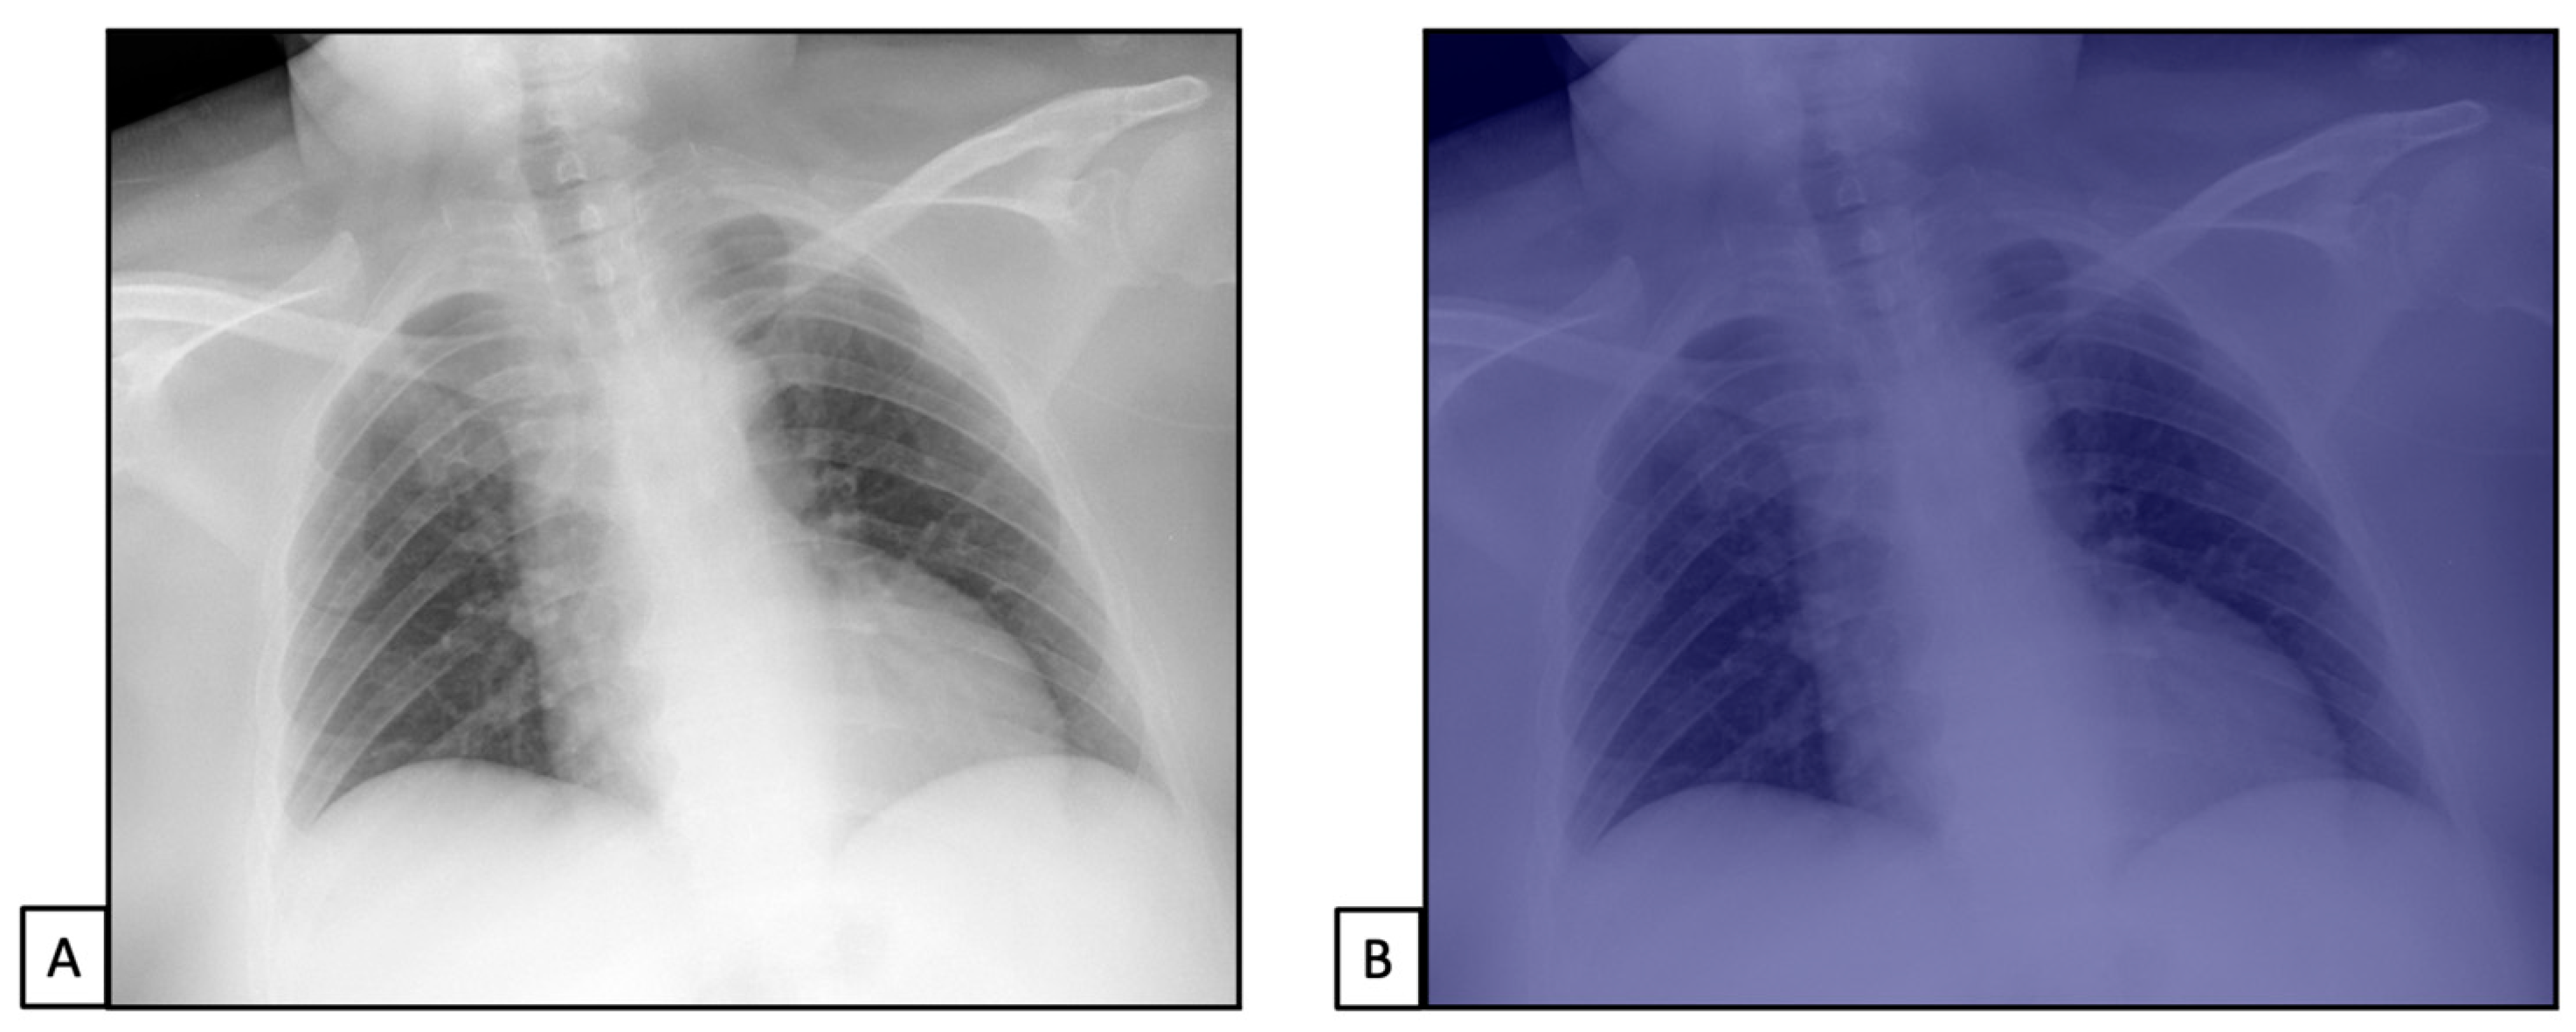

Figure 4.

Chest X-rays of patients admitted to the emergency department with respiratory distress and fever belonged to dataset 2. (A) represents CXR acquired at the bedside, showing compact typical opacities in the left lung lower zones. (B) represents AI system analysis, showing the pathological zones. The AI system reported a high suspicion of pneumonia, not typical for COVID-19 (99.99%). The final diagnosis was lung pneumonia due to Streptococcus pneumoniae.

Figure 5.

Chest X-rays of patients admitted to the emergency department with thoracic pain belonged to dataset 3. (A) represents CXR acquired at the bedside, showing no pathological findings. (B) represents AI system analysis, showing no pathological zones. The AI system reported a high suspicion of healthy subjects (98.5%). The final diagnosis was thoracic pain due to myocardial infarction.